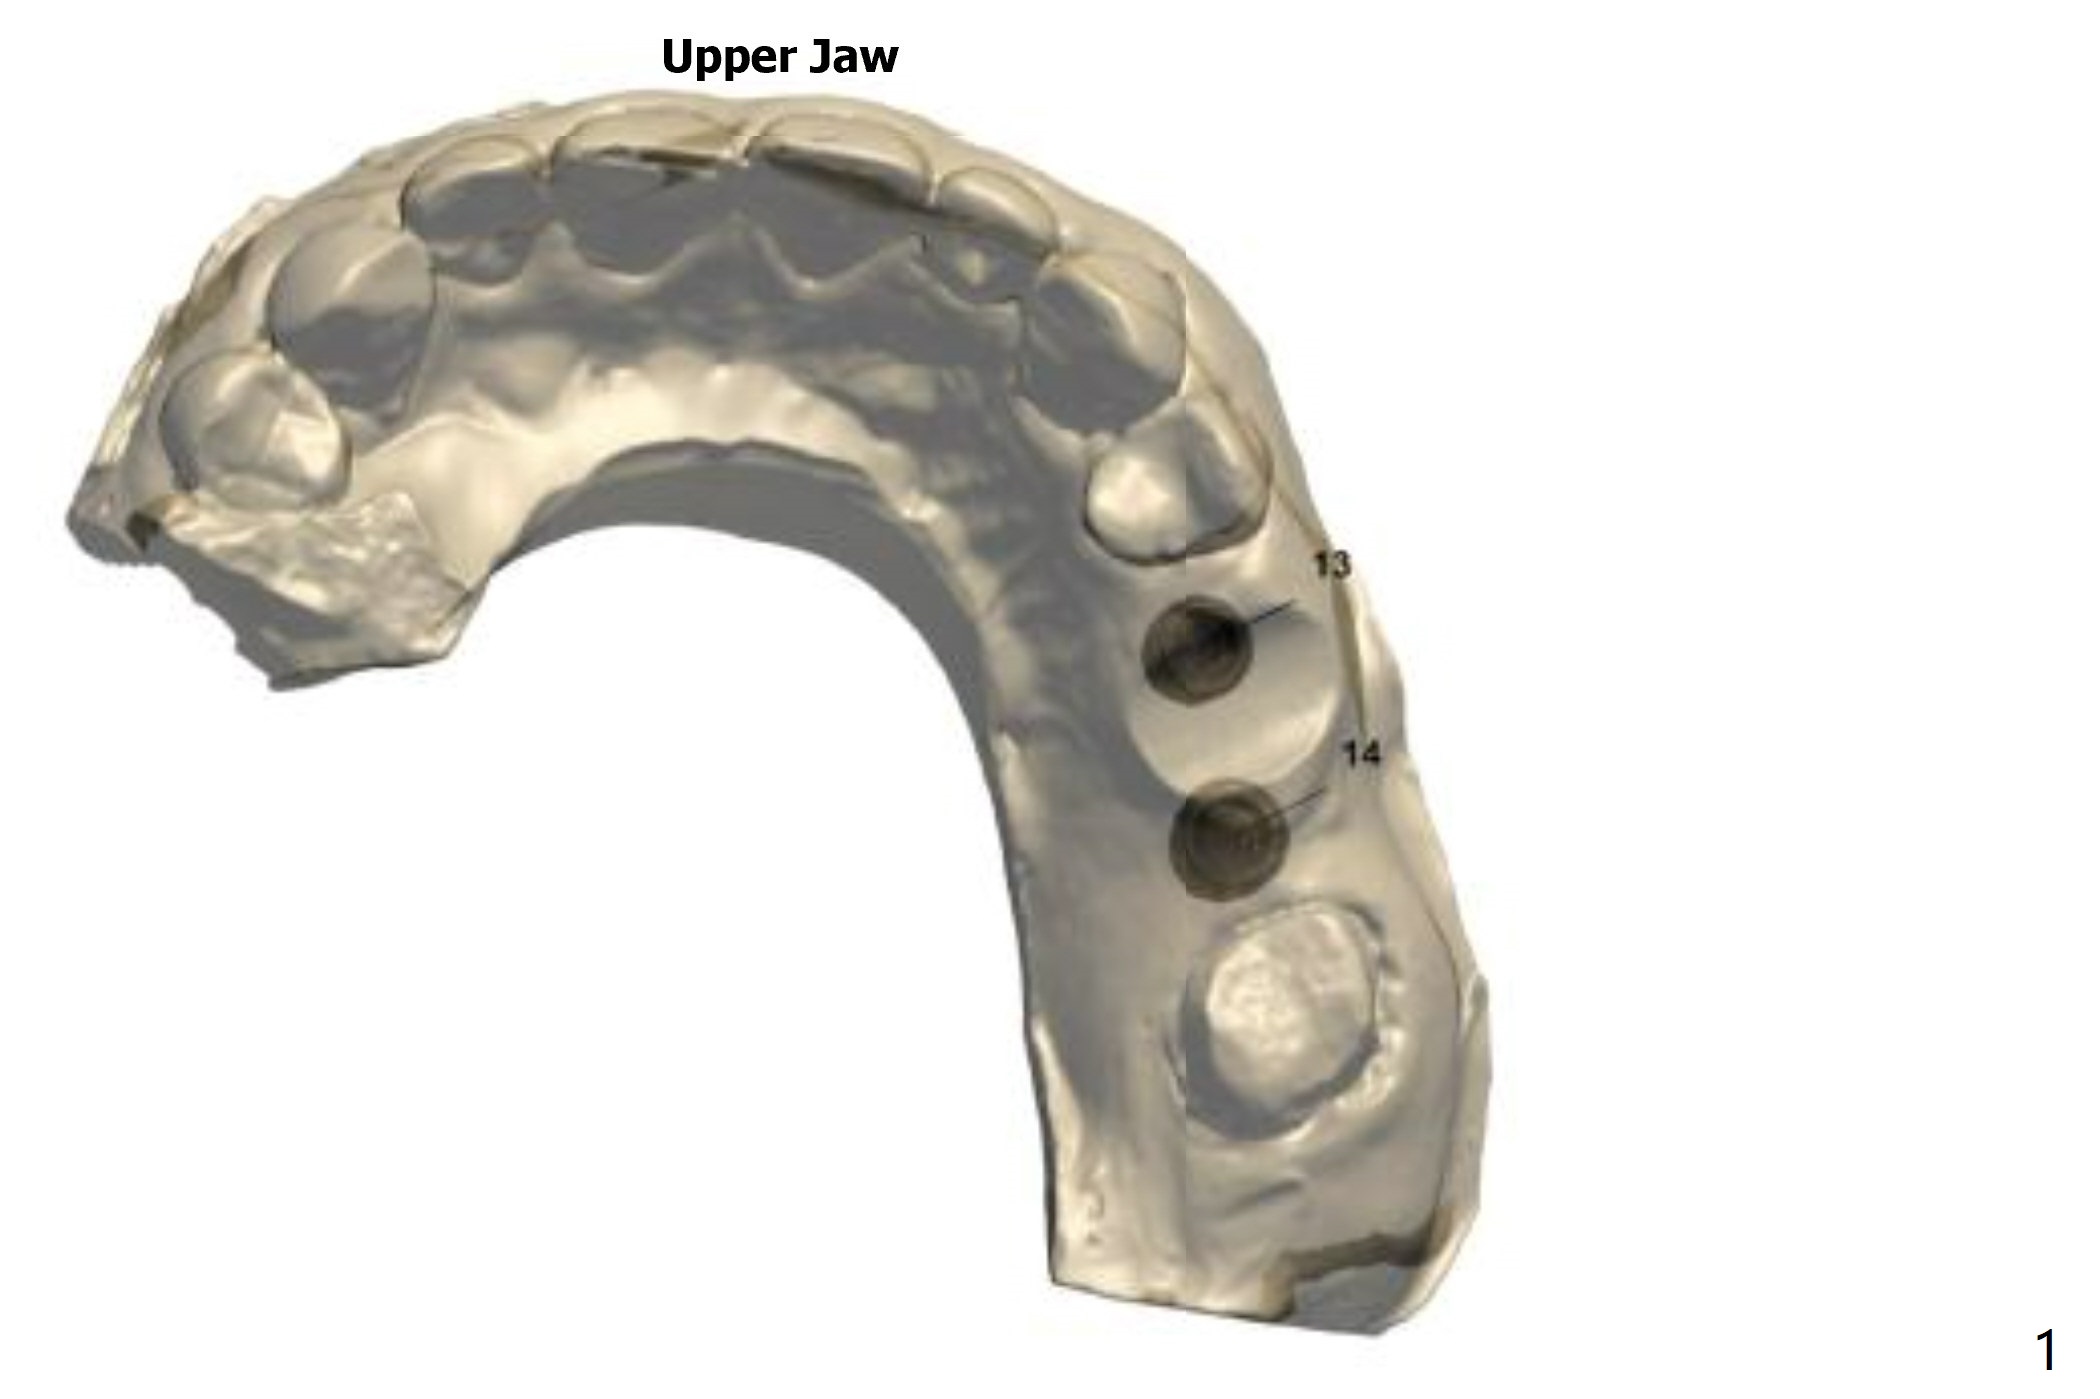

Return to Upper Molar Premolar Immediate Implant, Trajectory, Metronidazole